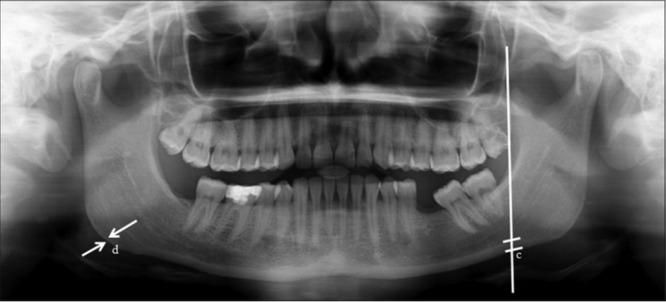

Patients aged 20 years to 40 years reporting to the Department of Oral Medicine and Radiology with and without a history of chronic areca nut chewing will be recruited. OPG will be collected for all recruited patients. The mandibular cortical index, panoramic mandibular index, gonial index, antegonial index, antegoinal notch depth, and mental index will be calculated.

招募年龄在20岁至40岁之间、有或无长期嚼槟榔史且到口腔医学与放射科就诊的患者。为所有招募的患者采集OPG。计算下颌骨皮质指数、全景下颌指数、角指数、角前切迹指数、角前切迹深度和颏孔指数。